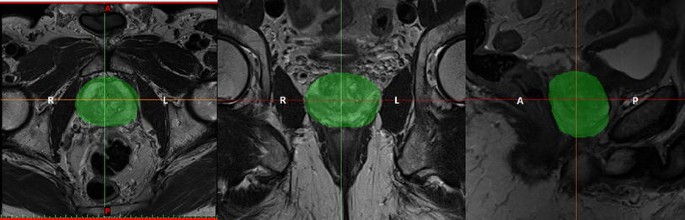

3D segmentation of prostate contour

Participants had 3T mpMRI scans before their preferred surgical treatment option (laparoscopic radical prostatectomy). Three planar views (axial, coronal and sagittal) of the prostate were obtained by T2-weighted images (T2WI); the thickness of each slice was 3 mm with 0.6 mm gap and the scan resolution for axial view of 0.63 × 0.63 mm2. After a detailed analysis of 2D pelvic images, the boundary of the prostate capsule was traced with the help of an experienced uro-radiologist and MIMICS software (Medical Image Segmentation for Engineering on Anatomy), and the segmentation of the prostate was done in one direction (mostly axial) and modified in the other two directions (as shown in Fig. 3). The model was saved as a stereolithography (STL) file.